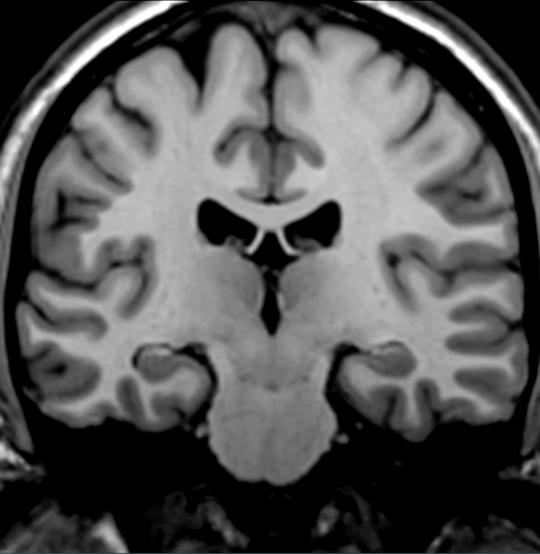

Locate the area of the cortex that receives projections from the medial geniculate.